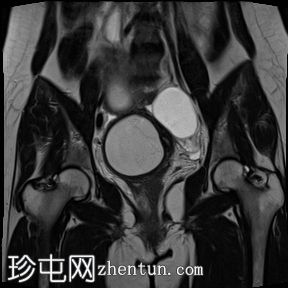

冠状位

T1加权像

子宫腔重复畸形,表现为两个子宫体和两个宫颈。

右侧宫颈和子宫腔明显扩张,内部血流信号显示中央狭窄,T1加权像呈高信号,T2加权像呈低信号,脂肪抑制序列图像上无信号下降,内部可见持续低信号灶。最大轴位和冠状位直径分别为约6.5 x 6.4 x 14.2 cm。可见该肿块向前压迫膀胱,向后推移右侧卵巢,并紧贴左侧宫颈。

双侧重复子宫腔的交界区完整,未见明显的肌层局灶性病变。左侧子宫内膜厚度正常。

左侧卵巢囊肿最大轴径和头尾径分别约为5.7 x 4.3 x 5.5厘米,T2加权像呈高信号,T1加权像呈低信号。